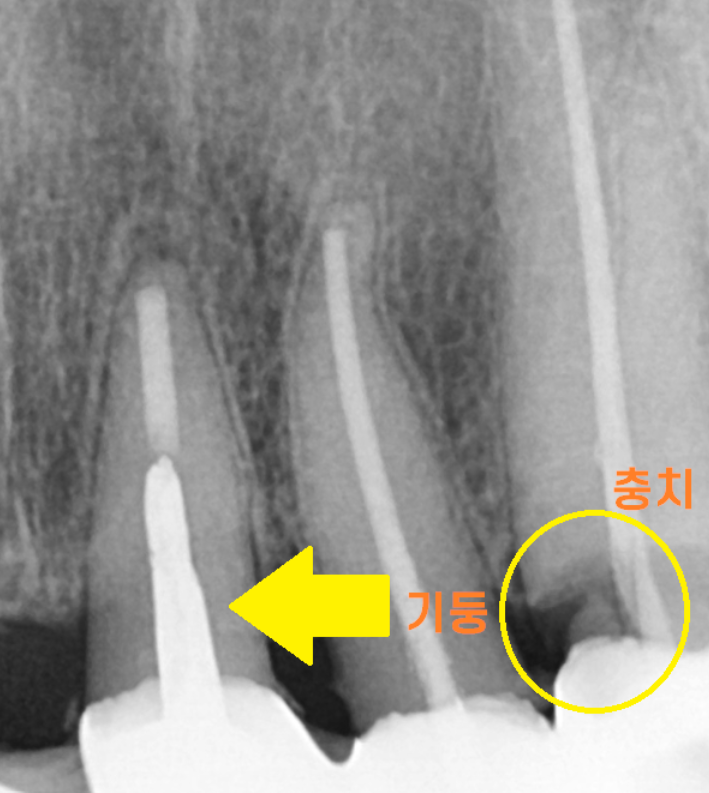

치아가 별로 안남을 때 치료하는 기둥이 박힌 치아가 2개

뿌리쪽 충치가 심한 치아 1개

치아가 거의 남아있지 않게 생겼습니다.

크라운 씌운 치아들은 주로 치아 목 부분

뿌리쪽이 썩는 이유가

보철 경계부위이기 때문에 그렇습니다.